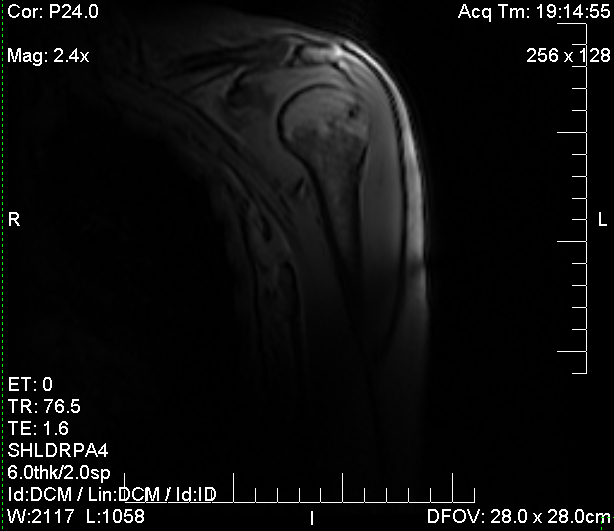

Frozen shoulder, MRI scan Stock Image C038/6266 Science Photo Library Frozen Shoulder Mri Find out more about the signs and. Adhesive capsulitis (also known as frozen shoulder) is a condition of the shoulder characterized by functional loss of both passive and active shoulder motion commonly associated. Frozen shoulder is when tissue and ligaments around your shoulder joint become inflamed, painful and stiff. Frozen shoulder can usually be diagnosed from signs and symptoms alone.. Frozen Shoulder Mri.